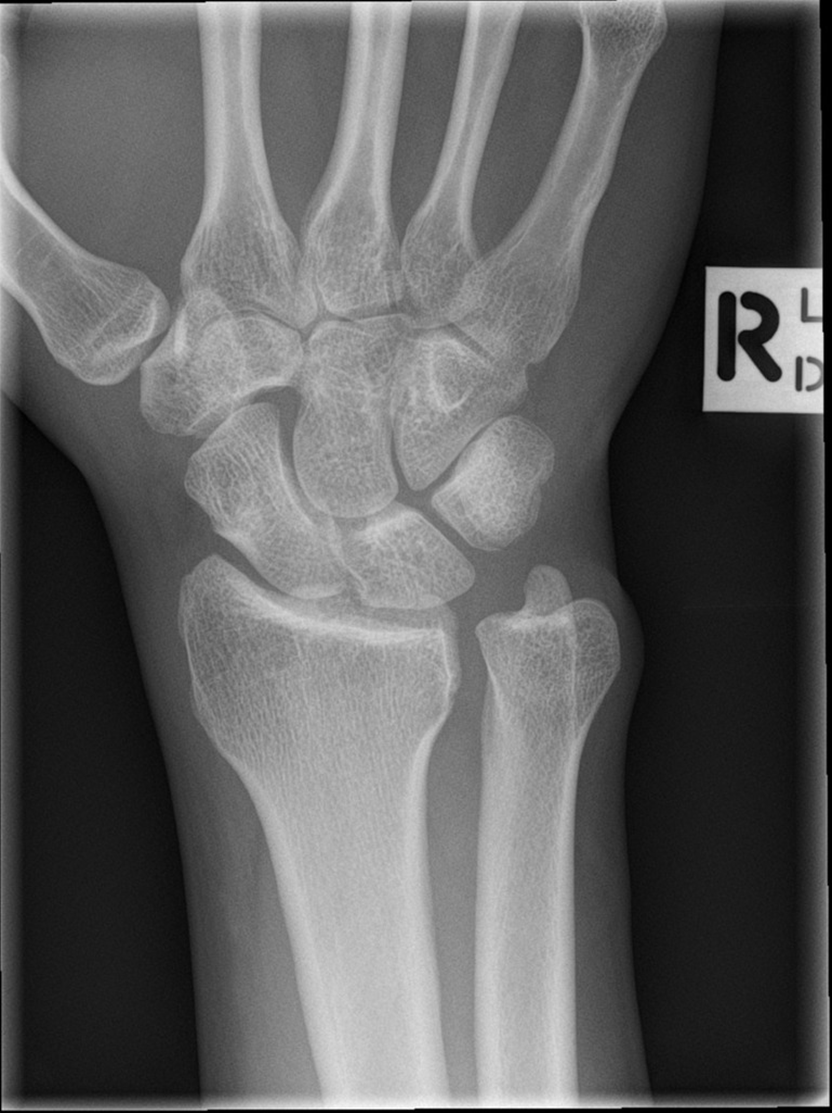

What view is this

PA wrist

What is 1

capitate

What is 16

trapezoid

What is 15

trapezium

What is 12

scaphoid

what is 6

lunate

what is 17

triquetrum

what is 8

pisiform

what is 18

ulna

what is 10

radius

what is 4

hamate